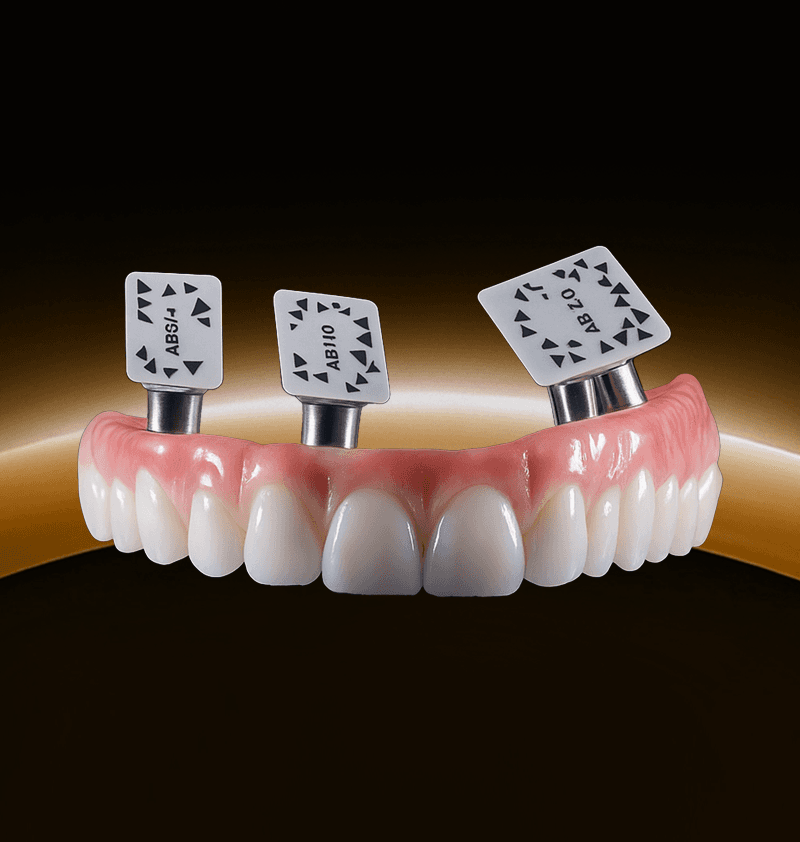

Seamless digital solutions for every step of the implant journey.

From scan to final delivery, 3Sixty streamlines your workflow with smart planning, precision guides, and real clinical support.

3Sixty is a digital dental lab with 150+ dental and technical experts supporting every case. From treatment planning to surgical guides and full-arch workflows like our groundbreaking Anatomic Guide®, we help streamline complex procedures. Trusted by over 3,000 dentists, we make digital implant dentistry simpler, faster, and more predictable.

"What I can appreciate about the [Anatomic Guide®] is that it will save you time and also will give you better guidance when placing the implants."

“Incredible merging of technology and know-how. I became a believer in the diamond latch. I know we can complete a dual arch case in under three hours.”